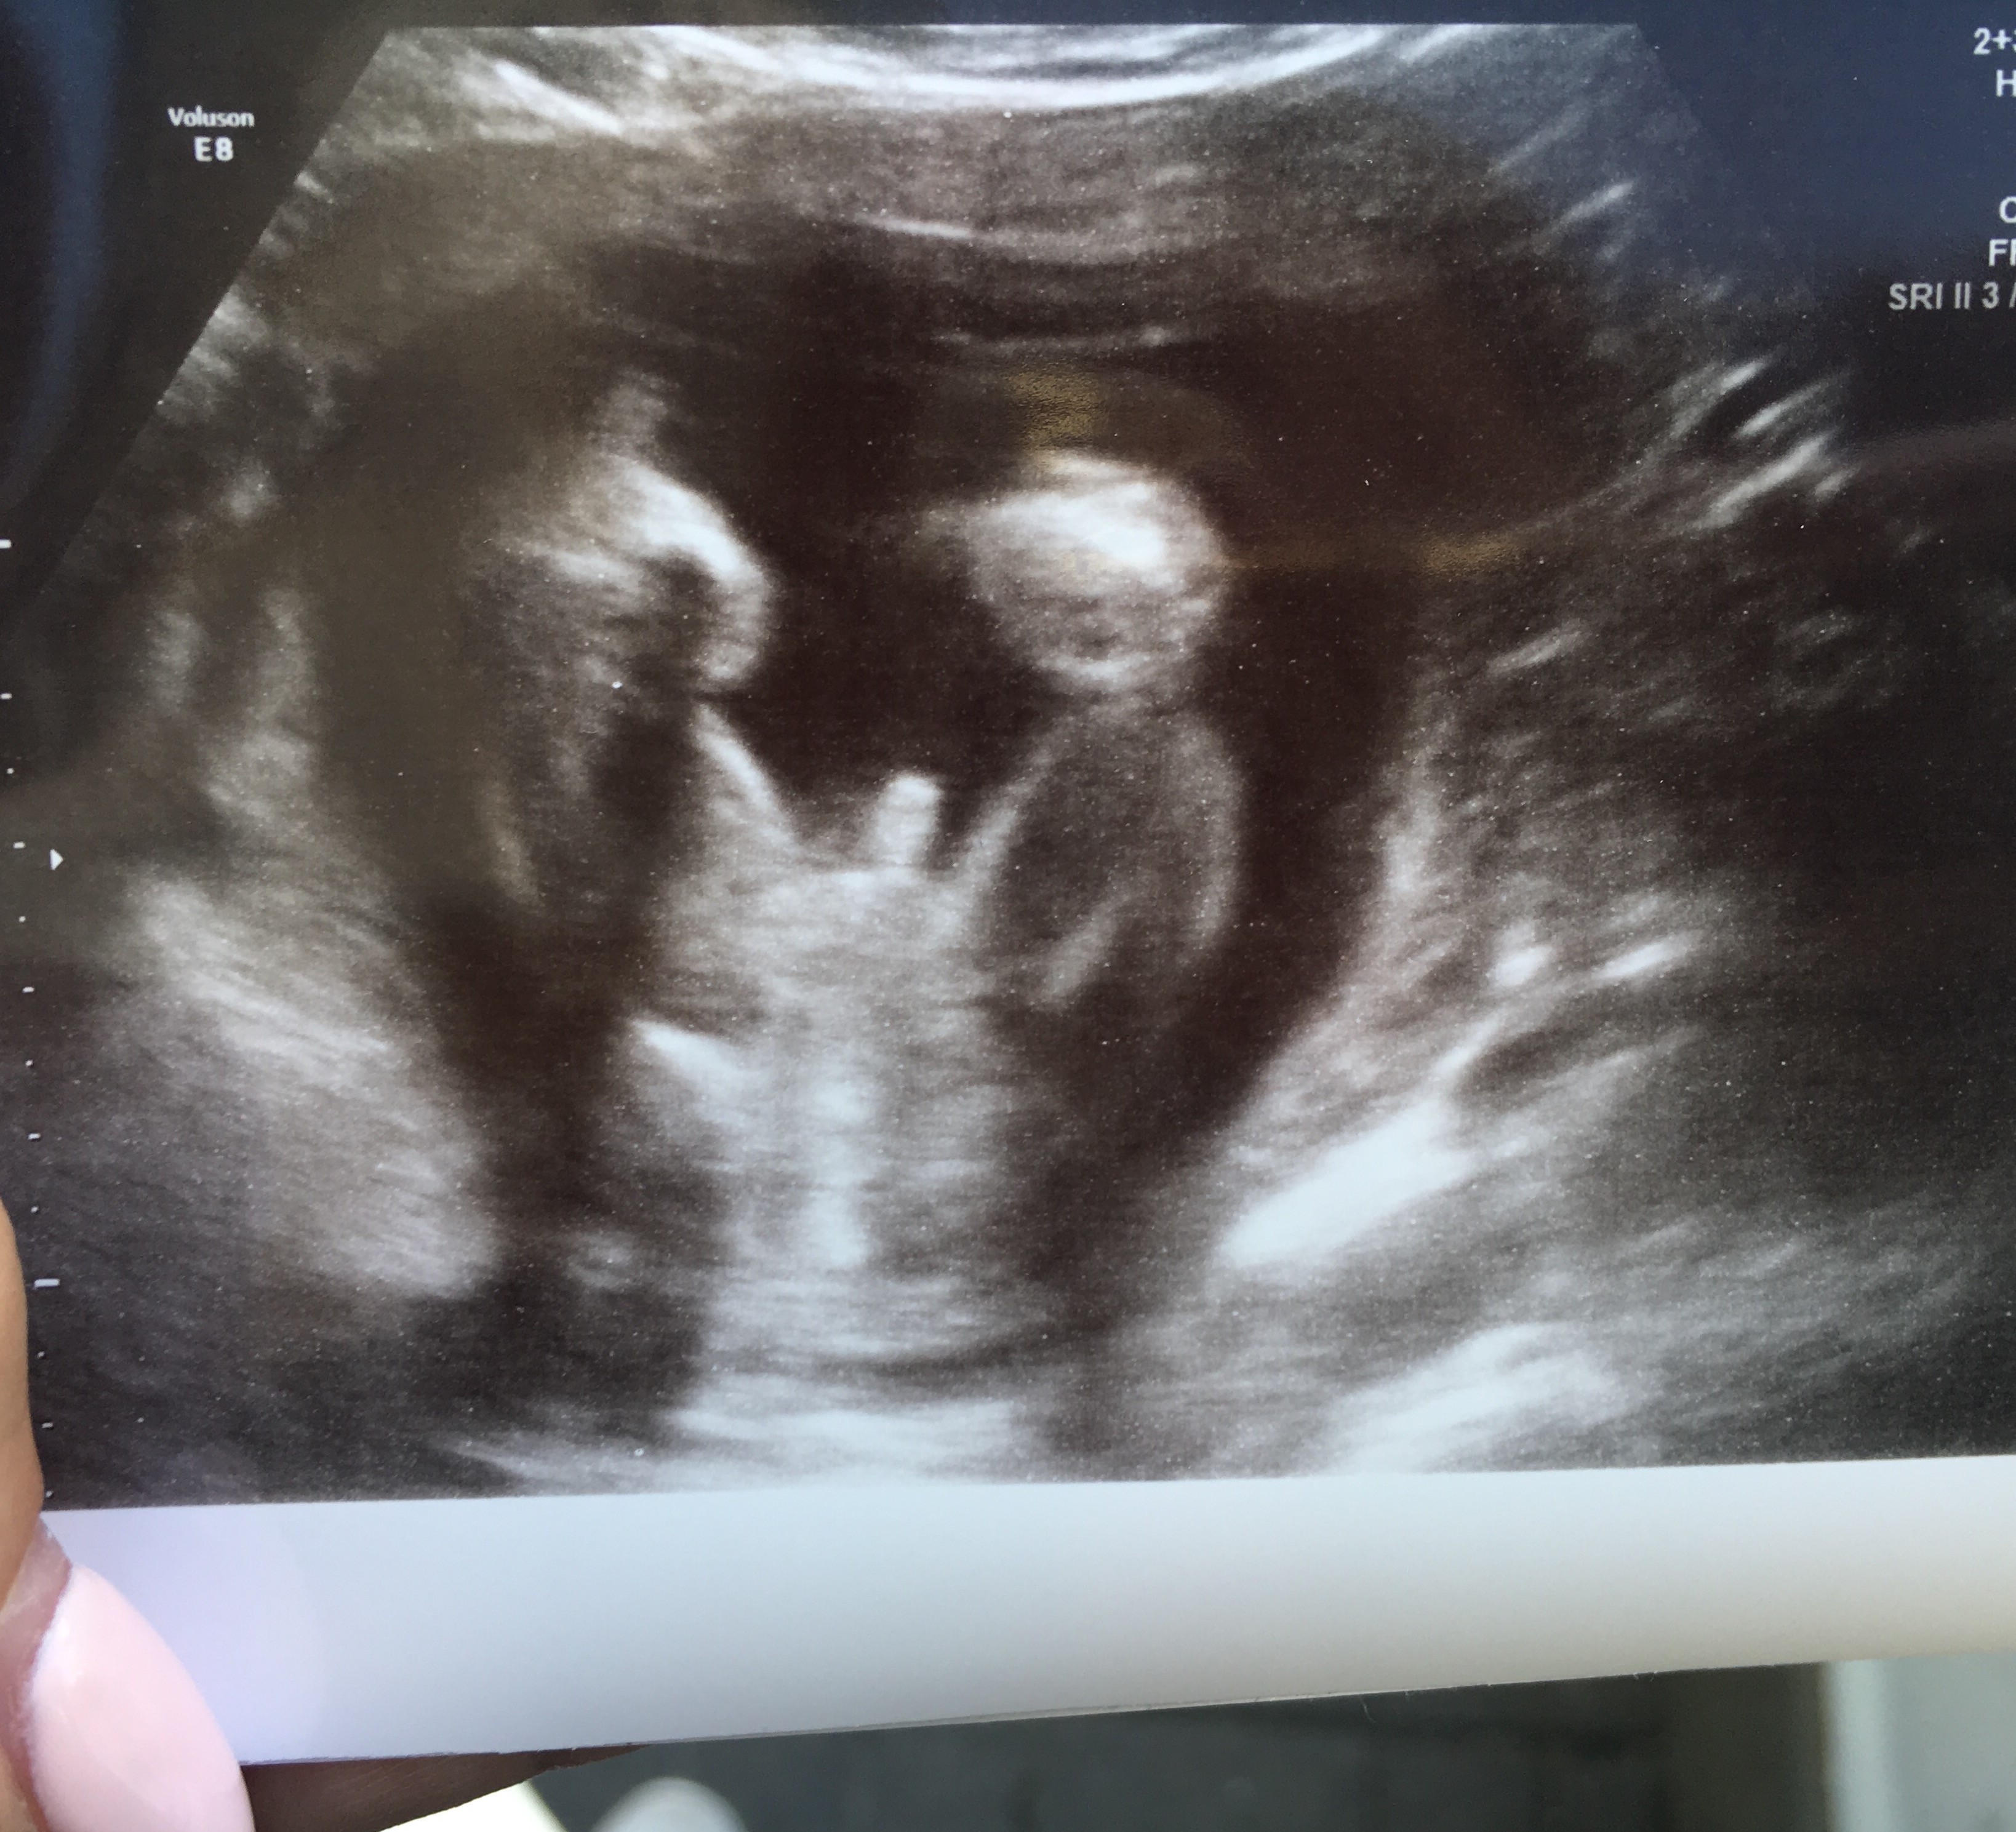

Usg chłopak czy dziewczynka

Witam w 19 tygodniu ciąży dowiedziałam się ze będę miała dziewczynkę w 20 tyg okazało się jednak , że to chłopak. Sama już nie wiem bo na jednym usg widać na pewno dziewuche a na drugim chłopca. Może to pempowina ?? Może ktoś mi pomoże rozwiązać ta zagadkę

• 4A8F5FF1-76CA-4DE0-AC12-5EDF08E820F2.jpg

4A8F5FF1-76CA-4DE0-AC12-5EDF08E820F2.jpg

596,4 KB · Wyświetleń: 44 141